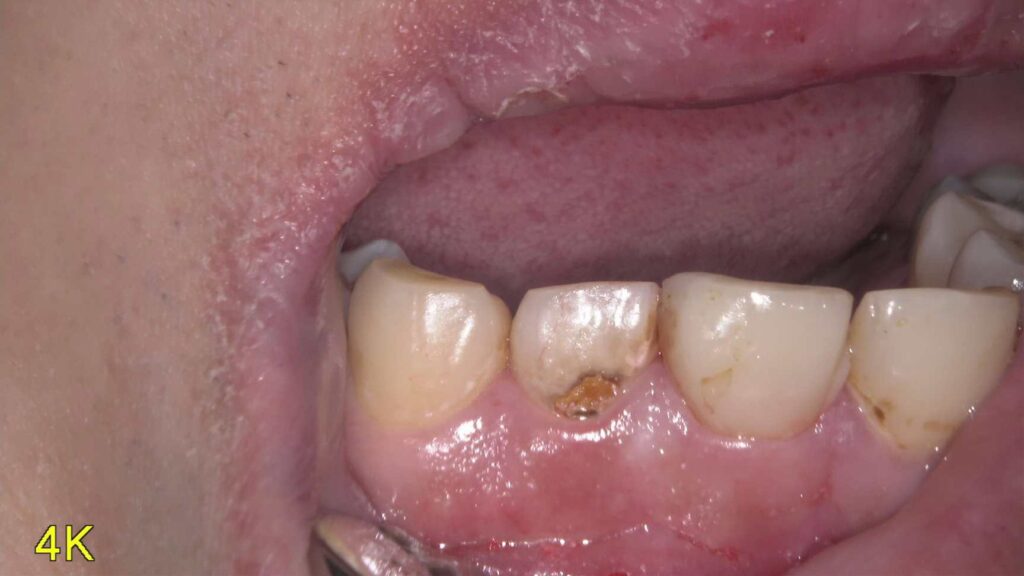

【治療ブログ】右上1番の「前歯の暗さ」が気になる—被せ物を外すと内部に強い汚染と変色がありました・・・

こんにちは、アバンダンスデンタル名古屋院長の伊佐津です。 今回は「右上1番(前歯)が暗く見えるのが気になる」とい…